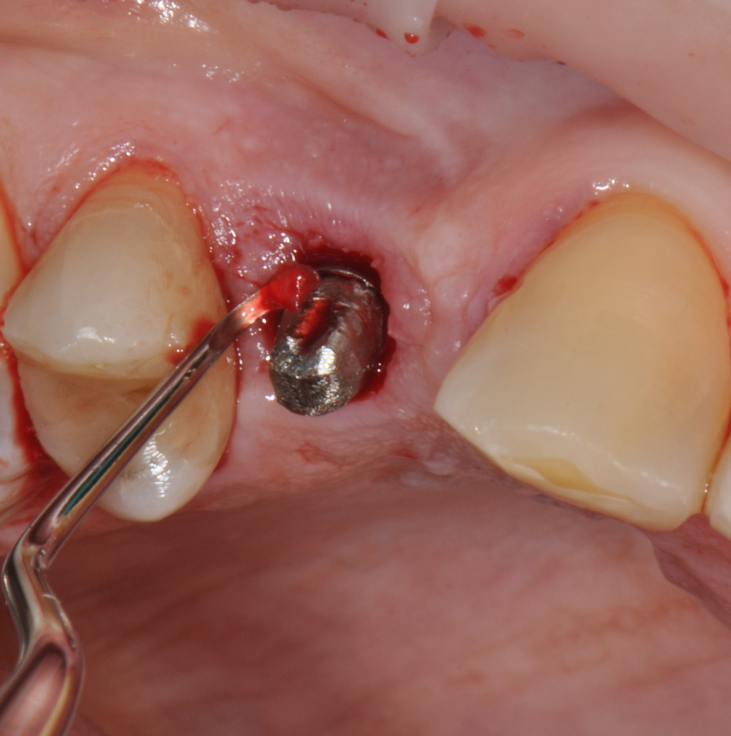

The parameters used to define peri-implant disease usually are: Probing Depth (PD), Crestal Bone Loss (CBL), Bleeding on Probing (BOP) and presence of suppuration and/or fistula.9 Peri-implant mucositis is characterised by soft tissues inflammation witnessed by BOP with or without PD deepening but no effects on the crestal bone while peri-implantitis is characterised by CBL, BOP alone or in conjunction with pus, with or without PD deepening. (Figs. 1, 2 and 3) display the diagnostic steps of a case of peri-implantitis. While mucositis allows a complete healing, peri-implantitis is not reversible.12

Fig.4: Case 1. Clinical appearance after the prosthetic crown removal.

Second step of prevention can be carried out during the surgical phase: a correct positioning of the fixture can help the technician in constructing a correct prosthesis and, consequently, the periodontologist in checking the implant health, the hygienist in cleaning effectively the peri-implant area13 and the patient in keeping an high standard home-care. An ineffective care leads to the development of inflammatory reactions that can be kept hidden under the the prostheses and be unrevealed until their removal. (Fig.4) Particular attention should be given to reach an appropriate amount of keratinized peri-implant tissue: its presence can be beneficial for the maintenance of an adeguate oral hygiene.13 Long abutments and implant placement at sub-mucosal level cannot be considered a good choice from the periodontal point of view since they may create a deep probing depth since the very beginning of the implant-born restorations’ life.13